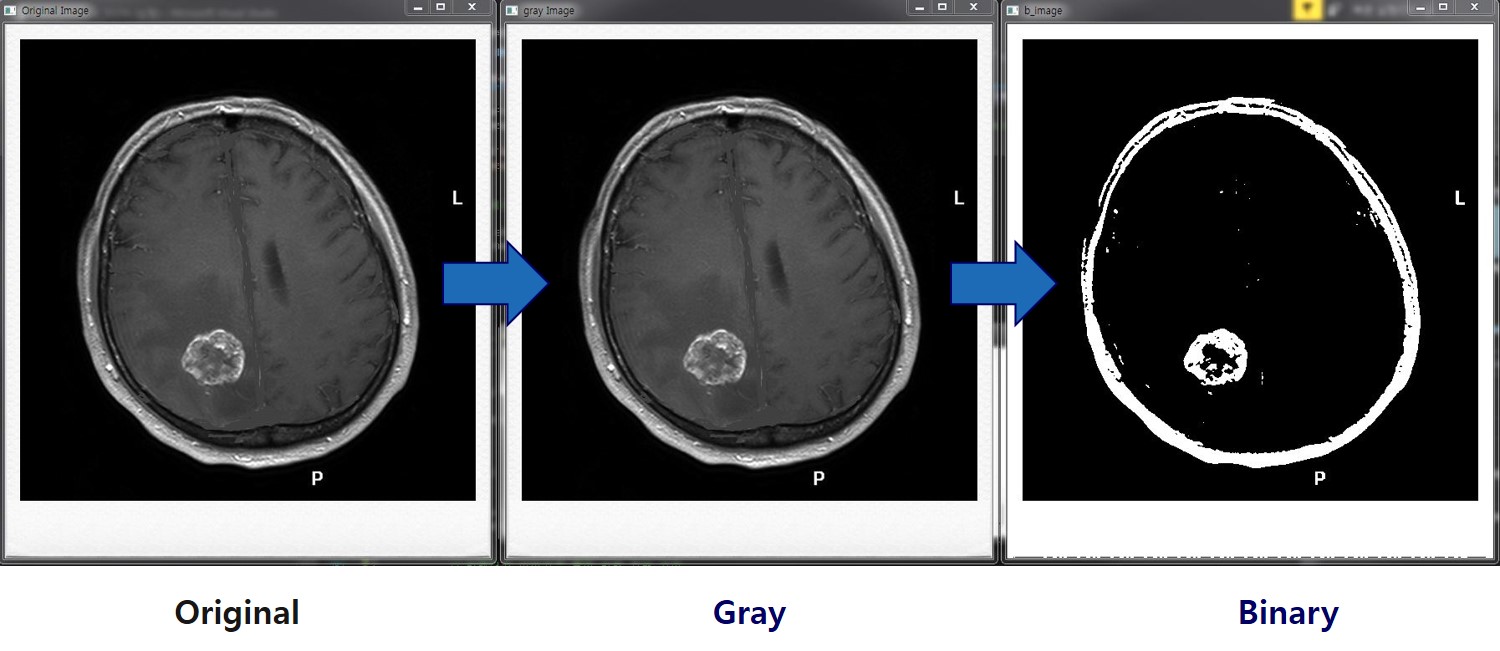

이미지처리를 이용해 DICOM 영상에서 뇌종양 부위 식별에 도움을 주는 알고리즘을 개발함. DICOM 영상데이터를 OpenCV에서 처리가능한 데이터로 변환하고, 이진화 및 모폴로지를 통해 전처리함. 실제 뇌종양 영역의 데이터 분포와 비슷한 양상의 영역을 후보군으로 검출하여 뇌종양 영역 식별을 용이하게함.